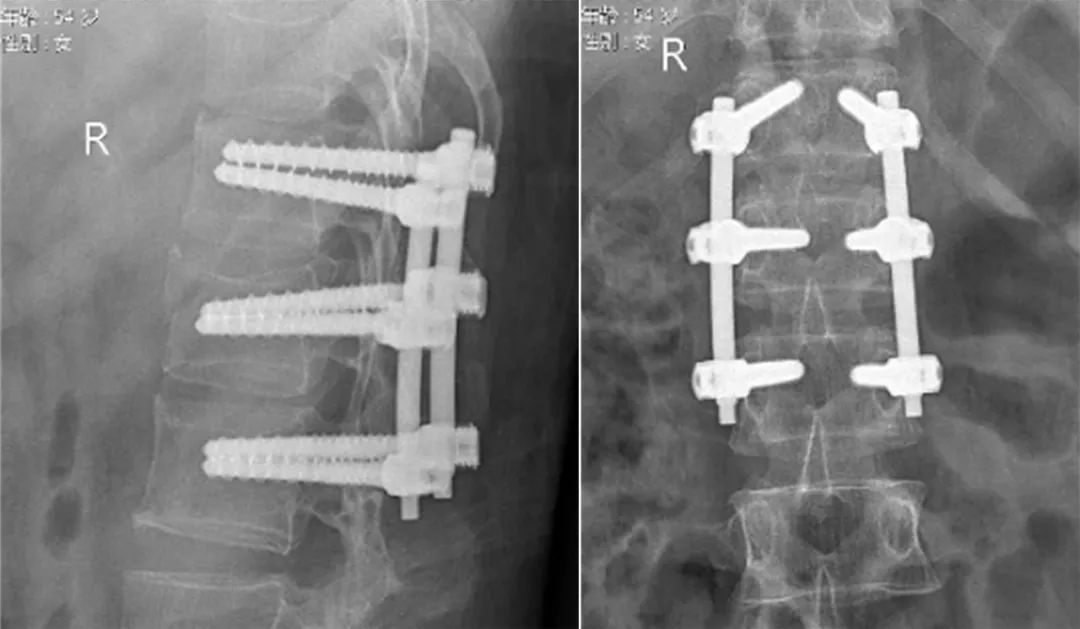

椎管减压:凭借精湛的医术,精细地清除突入椎管的骨碎片,如同拆除一颗颗 “定时炸弹”,彻底解除神经压迫;椎体重建:利用椎弓根钉棒系统,小心翼翼地恢复椎体高度与生理曲度,为脊柱重新搭建稳固的 “梁柱”;稳定固定:6枚钛合金螺钉植入体内,构建起坚不可摧的「三维固定系统」,让脊柱重获稳定。这场手术充分展现了医疗团队的超高水准:术中出血仅50ml,远低于同类手术平均200-400ml的出血量;全程神经监测保驾护航,实现零神经损伤;美容缝合的切口,瘢痕竟小于8cm!每一个数字背后,都是医护团队高超的技术与严谨的态度。